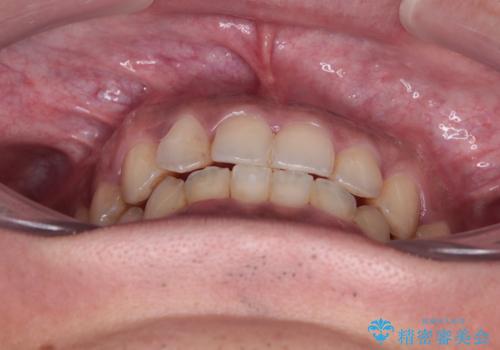

- 前歯のデコボコを気にして来院された患者様です。

前歯が90度近く捻れていたため、しっかりと治すことを考えるとワイヤー矯正の方がおすすめではありましたが、本人の希望によりインビザラインを用いて矯正治療を行うこととしました。

途中2年強の来院がなく、改善されていたデコボコが元に戻ったり、装着時間が不足しており前歯のデコボコは十分に改善することはできませんでしたが、5年間の有効期限内で可能な限り歯列を整えることができました。